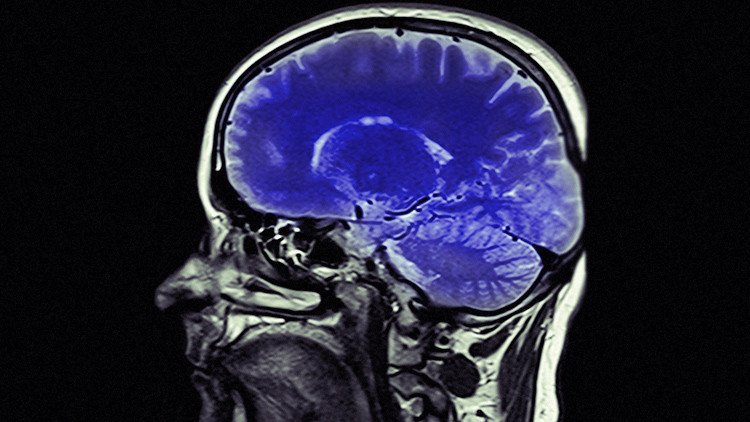

Los métodos actuales de tratamiento incluyen una estimulación eléctrica transcraneal, es decir, la aplicación de electricidad de una intensidad directa (continua) de corriente entre dos electrodos en la cabeza, y sus usuarios destacan las mejoras en la memoria, en la capacidad de cálculo matemático o en la resolución de problemas. Y podría ir más allá.

En 2013, el doctor Shapour Jaberzadeh y su equipo del Departamento de Fisioterapia de la Universidad de Monash, Australia, descubrieron una nueva técnica que en comparación con la estimulación eléctrica convencional aumenta significativamente la excitabilidad del cerebro.

"Este tratamiento, que llamamos 'estimulación transcraneal de corriente pulsada' (TPCS, por sus siglas en inglés), es una forma de estimulación no constante con periodos de 'on' y 'off', o pulsaciones entre los dos electrodos", explicó Jaberzadeh.

"Hemos descubierto que este nuevo tratamiento produce grandes cambios en el cerebro y que el intervalo entre impulsos también tiene efecto. Cuanto más corto sea el intervalo entre impulsos tanto mayor es el efecto de la excitabilidad del cerebro".

El doctor Jaberzadeh afirma que la técnica tiene implicaciones interesantes para toda una serie de condiciones en las que "la mejora de la excitabilidad del cerebro" tiene un efecto terapéutico. Estas condiciones incluyen los efectos de la formación específica de la tarea repetitiva para el tratamiento del accidente cerebrovascular y otros trastornos neurológicos, trastornos mentales y del tratamiento del dolor.